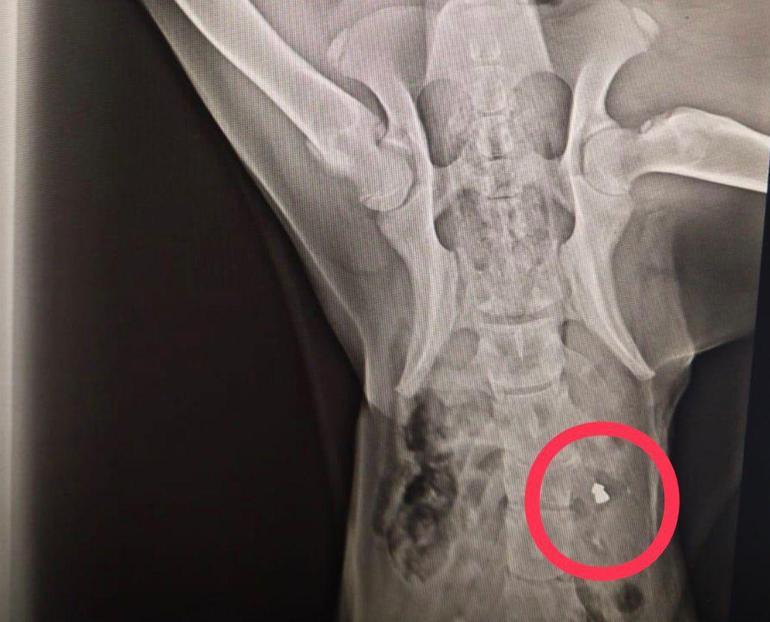

Perşembe ilçesi Efirli Mahallesi’nde biri bugün olmak üzere son 10 gün içerisinde ‘domuz kurşunu’ ile vurulmuş halde yaralı bulunan 3 sokak köpeği, tedavi edilmek üzere hayvanseverler tarafından Altınordu ilçesindeki Veteriner Hekim Taner Canbulut’a ait kliniğe getirildi. Burada yapılan kontrollerde, 3 köpeğin de vücutlarının çeşitli yerlerinde ‘domuz kurşunu’ tespit edildi. Bu süreçte kliniğe getirilen yaralı köpeklerden 2’sinin öldüğünü ve birinin ise tedavisinin devam ettiğini belirten Canbulut, “Son günlerde sokak canlarının tüfekle vurulması durumuyla karşı karşıyayız. 10 gün önce sırt bölgesinden vurulmuş bir köpek getirildi ve müdahale etmemize rağmen kurtaramadık. Bu olaydan kısa bir süre sonra aynı şekilde vurulmuş bir köpek daha buraya getirildi. Getiren hayvanseverler, otomobil çarpması sanmış ama burada tedavi ederken onun da aynı şekilde domuz kurşunu ile vurulmuş olduğunu tespit ettik. Kurşunu çıkardık ve şu anda durumu iyi. Bugün ise domuz kurşunu ile vurulmuş başka bir köpek daha getirildi. Maalesef felç olmuş ve kurtarılma şansı yoktu. Bu nedenle uyutmak zorunda kaldık. Çok üzgünüz. Bunu yapan kişi veya kişilerin yakalanmasını istiyoruz. Bu yapılanlara ‘dur’ denmesi gerekiyor. Bu hepimizin insani, vicdani ve ahlaki vazifesi diye düşünüyoruz” dedi.